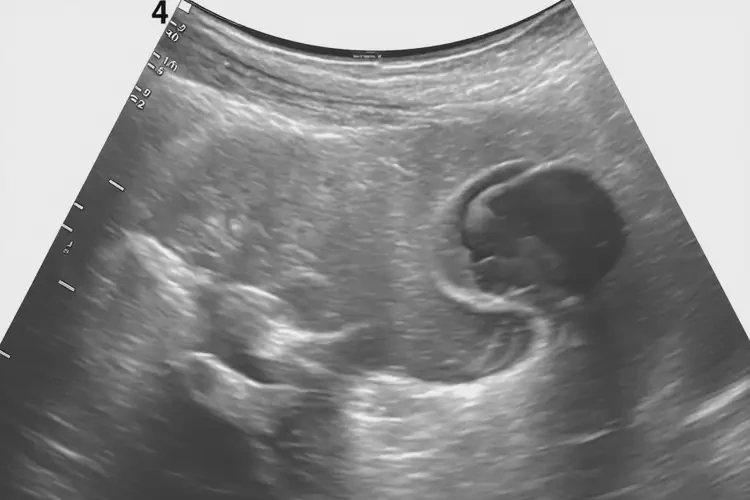

孕12周5天胎心160还要保胎吗(图1)